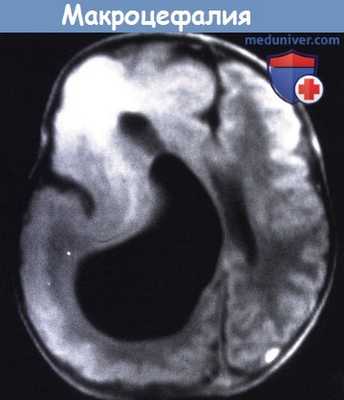

Т1 - взвешенное изображение МРТ пациента в возрасте пяти месяцев.

Большое правое полушарие, с патологически утолщенной корой и несколькими бороздами.

Значительно увеличенный желудочек и аномальный сигнал от лобного белого вещества.